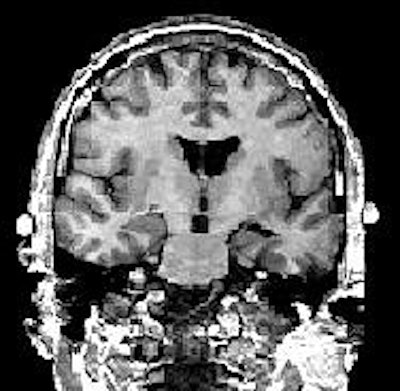

| Above, regions of interest (ROI) examined in MRI study of patients with first-episode schizophrenia or affective psychosis and normal comparison subjects. Top (A) is a 1.5-mm coronal slice of the temporal lobe; the ROI used to evaluate the temporal structures are outlines. The gray matter of the superior temporal gyrus is shown in red (subject left) and green (subject right); more medially, the amygdala-hippocampal complex is shown in orange (left) and blue (right) with the parahippocampal gyrus underneath in pink (left) and purple (right). Below, a left lateral view of a 3D reconstruction of the cortical surface with the anterior superior temporal gyrus (light pink) and posterior superior temporal gyrus (red). |

![]() |

| Same subject. Above and below, axial MRI is used to present top-down views of the 3D reconstruction of the amygdala-hippocampal complex and parahippocampal gyrus. All images: Figure 1, Hirayasu Y, Shenton ME, Salisbury DF, et al. "Lower Left Temporal Lobe MRI Volumes in Patients with First-Episode Schizophrenia Compared with Psychotic Patients With First-Episode Affective Disorder and Normal Subjects," (Am J Psychiatry 1998; 155:1384-1391). |